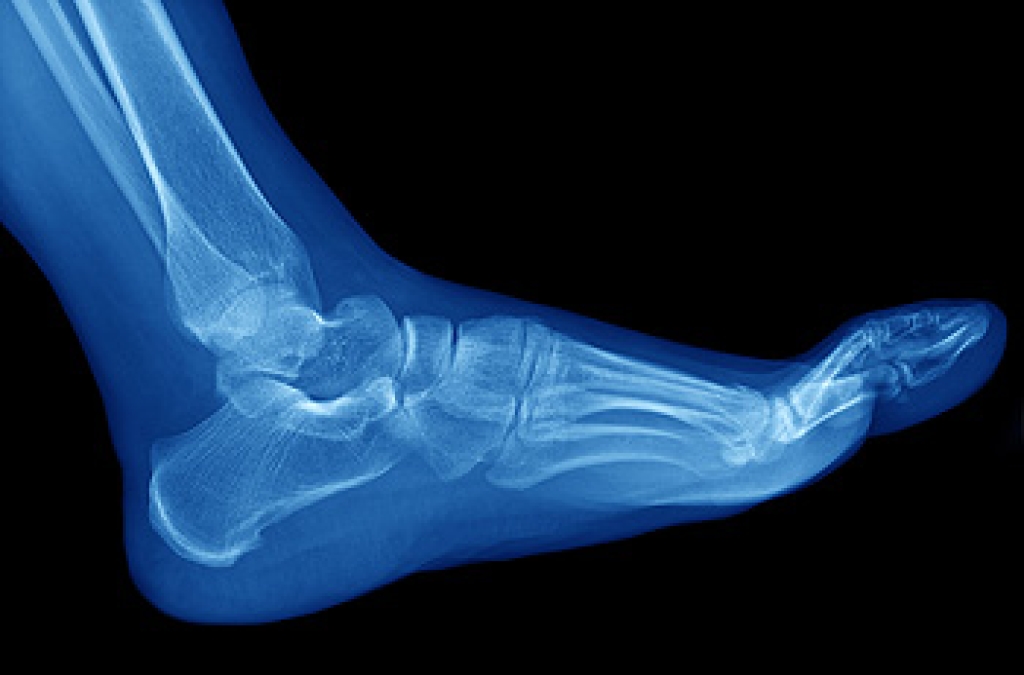

Stress fractures in the feet are a common injury, particularly among athletes. They can be caused by any activity that puts increased pressure on the feet, from playing a high impact sport to starting a new workout routine. A sudden increase in activity, for example, running for much longer than usual, can overload the bones in your feet. Changing the surface that you train on can have a similar effect, specifically if you are moving from a soft surface, like turf, to a hard one like asphalt. Having an improper running technique or wearing the wrong shoes can also lead to stress fractures. If you are suffering from any type of foot pain, please seek the care of a podiatrist.

Stress fractures are the result of repetitive force being placed on the bone. Since the lower leg and feet often carry most of the body’s weight, stress fractures are likely to occur in these areas. If you rush into a new exercise, you are more likely to develop a stress fracture since you are starting too much, too soon. Pain resulting from stress fractures may go unnoticed at first, however it may start to worsen over time.